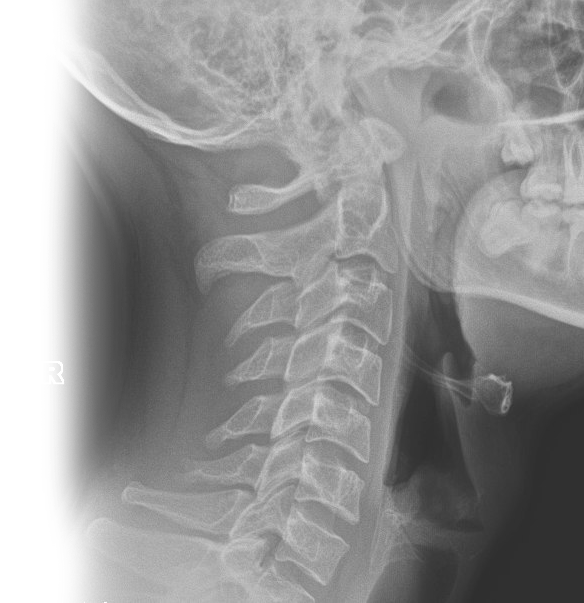

Рентгенография гортани в боковой проекции

Рентгенография гортани в боковой проекции (по Земцову) – важный метод прицельного исследования, который позволяет оценить состояние гортано-глотки. Диагностическая услуга выполняется одной проекции.

Исследование позволяет выявить сужение просвета гортани различной этиологии: опухолевой, инфекционной, инородные тела.